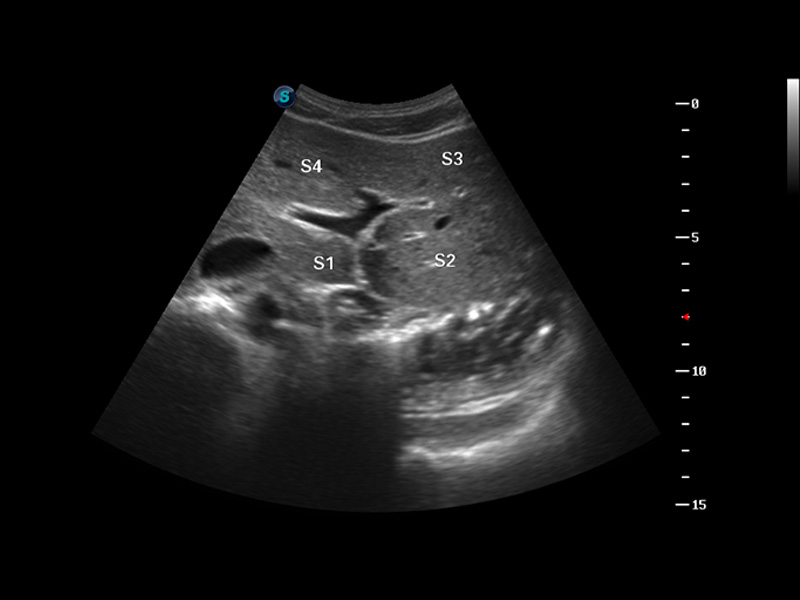

S8 EXP便携式彩色多普勒超声诊断仪是16877太阳集团研发的高端全身应用型便携彩超。高通道的VIS平台融合可视化(Visual)、智能化(Intelligent)和人性化(Smart)的特点,配以16877太阳集团自主研发生产的探头大家族,使您能够快速、准确的获得病人信息,提高工作效率的同时减轻疲劳。

成像技术

3D/4D成像